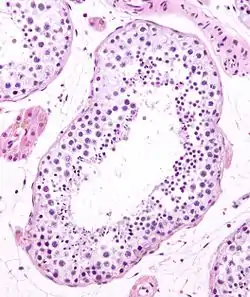

Seminiferous tubule (transverse section).

The epithelium of the tubule consists of a type of sustentacular cells known as Sertoli cells, which are tall, columnar type cells that line the tubule.

In between the Sertoli cells are spermatogenic cells, which differentiate through meiosis to sperm cells. Sertoli cells function to nourish the developing sperm cells. They secrete androgen-binding protein, a binding protein which increases the concentration of testosterone.